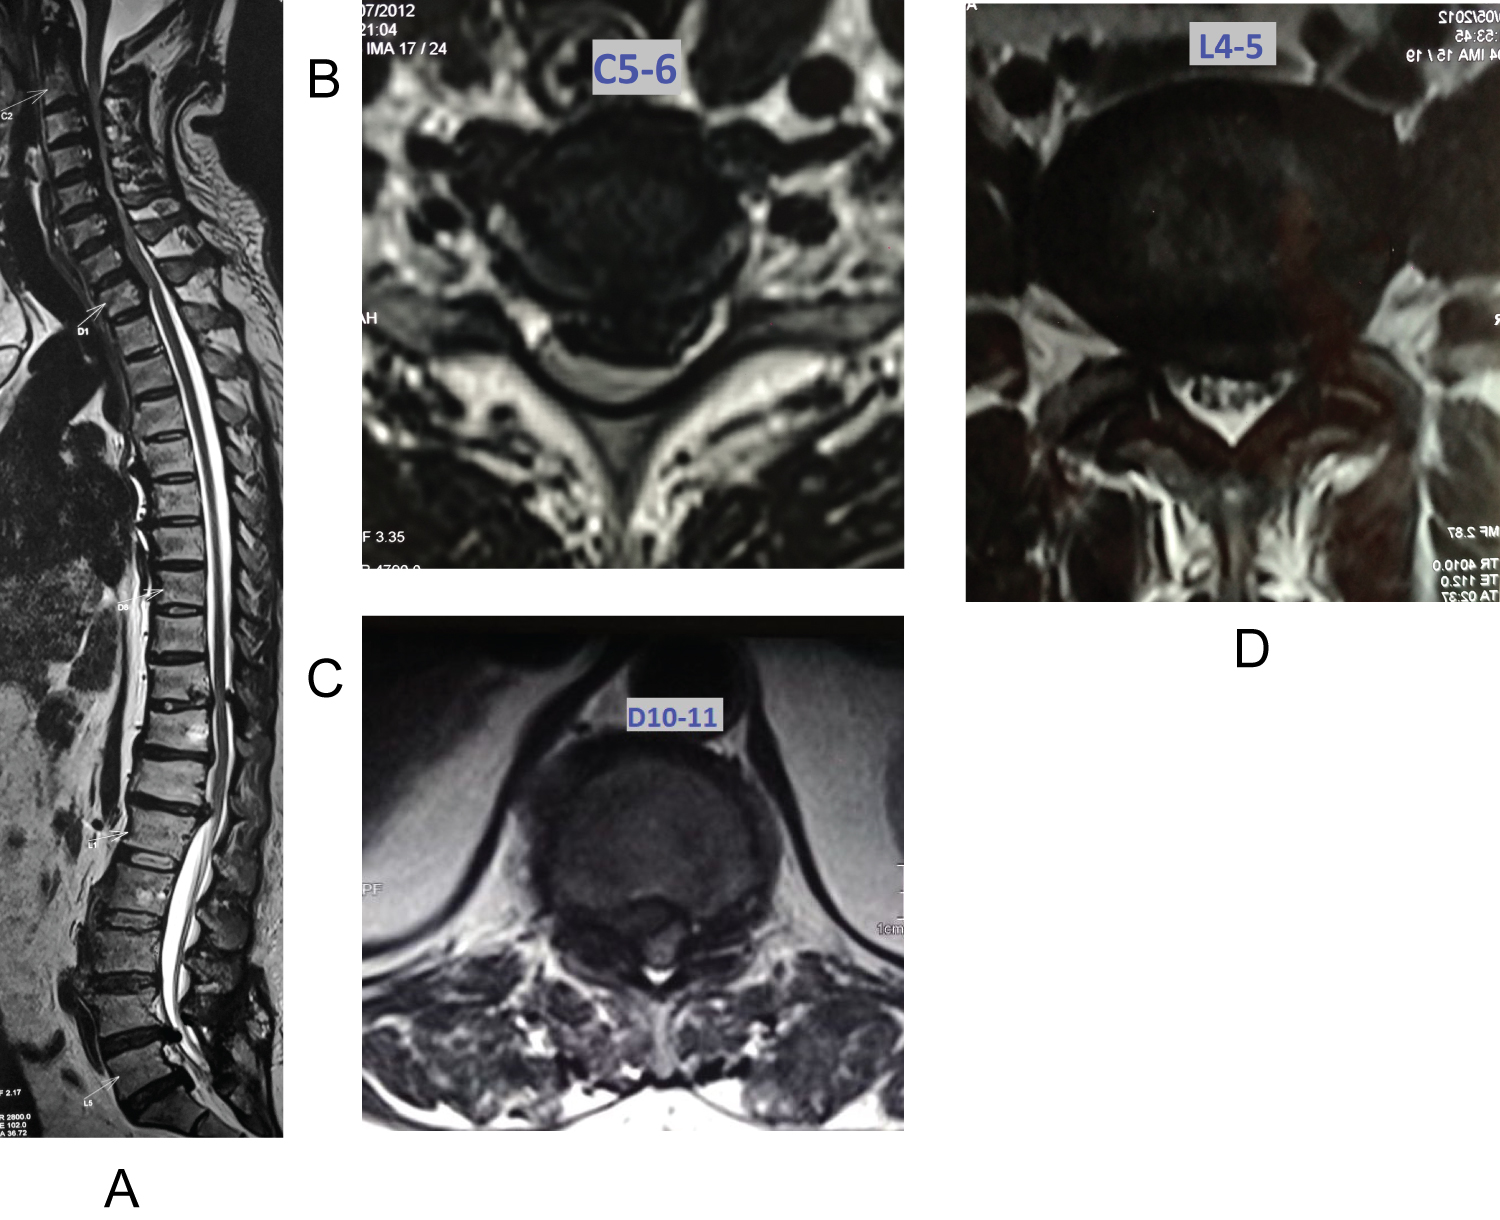

A 71-years-old female, a domestic worker had a fall at home 1 year prior to presentation complicated by chronic back pain and bilateral leg pain without claudication on clinical presentation, she reported a 3-month-old history of loss of balance while walking, worsening leg weakness, with numbness in both of her forearms and hands, with difficulty while dressing up and combing the hair. He had increased urinary frequency and occasional constipation since 3 weeks.

On examination, Power in both upper limbs and lower limbs was 4.Lower limbs were more spastic as compared to the upper limbs. Both upper and lower limbs showed hyper-reflexia with positive Babinski's. Grip release test was positive. Patient was a known diabetic and hypothyroid since 15 years and was on regular medications. MRI Cervical spine with whole spine screening revealed Triple-Region Spinal Stenosis. MRI of Cervical spine revealed severe canal stenosis secondary to Ossified Posterior Longitudinal Ligament from C3-T1. Signals of myelomalacia were present at these levels. Thoracic spine showed cord compression due to hypertrophied ligamentum flavum at D10-11 with cord oedema. Lumbar spine had canal stenosis at L4-5 levels.

Management: In view of cord signals in cervical and thoracic spine, hyper-reflexia in all 4 limbs Posterior Cervical decompression (C3-T1 decompression with Lateral mass fixation) and thoracic decompression (D10-11 posterior decompression with Left facetectomy and fusion) was carried out in first stage in a same sitting by two spine surgeons simultaneously. Patients gait improved over 6 months from Nurick Grade 3 to Nurick Grade 2, but bladder symptoms didn't resolve. Patient gradually started having worsening of bilateral leg pain and claudication so was operated L4-5 posterior decompression after 6 months after trying conservative management (Figure 3).

Figure 3: Whole spine sagittal cut showing TRSS at C3-T1, D10-11, L4-5. Axial section at the level with maximum compression - Cervical cord at C5-6, Thoracic at D10-11, lumbar at L4-5. View Figure 3